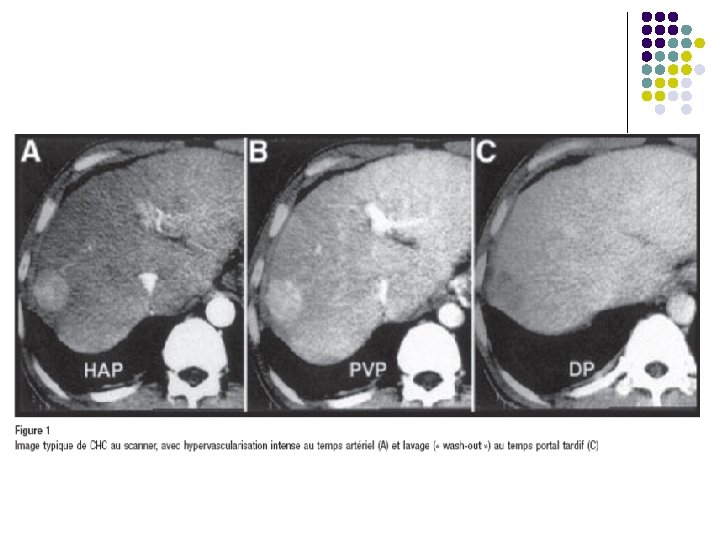

l Diagnostic de CHC l Caractéristiques évocateurs en TDM: Nodule hypervascularisé au temps artériel précoce avec lavage tardif « wash-out » l Critères diagnostiques positifs sur foie cirrhotique l l Histologique compatible ou Nodule < 1 cm: surveillance échographique / 3 mois ou Nodule 1 à 2 cm: 2 images typiques sur TDM et IRM ou Nodule > 2 cm: image hypervascularisée + wash out ou AFP > 200 mcg/l American Association for the Study of liver Diseases. 2005